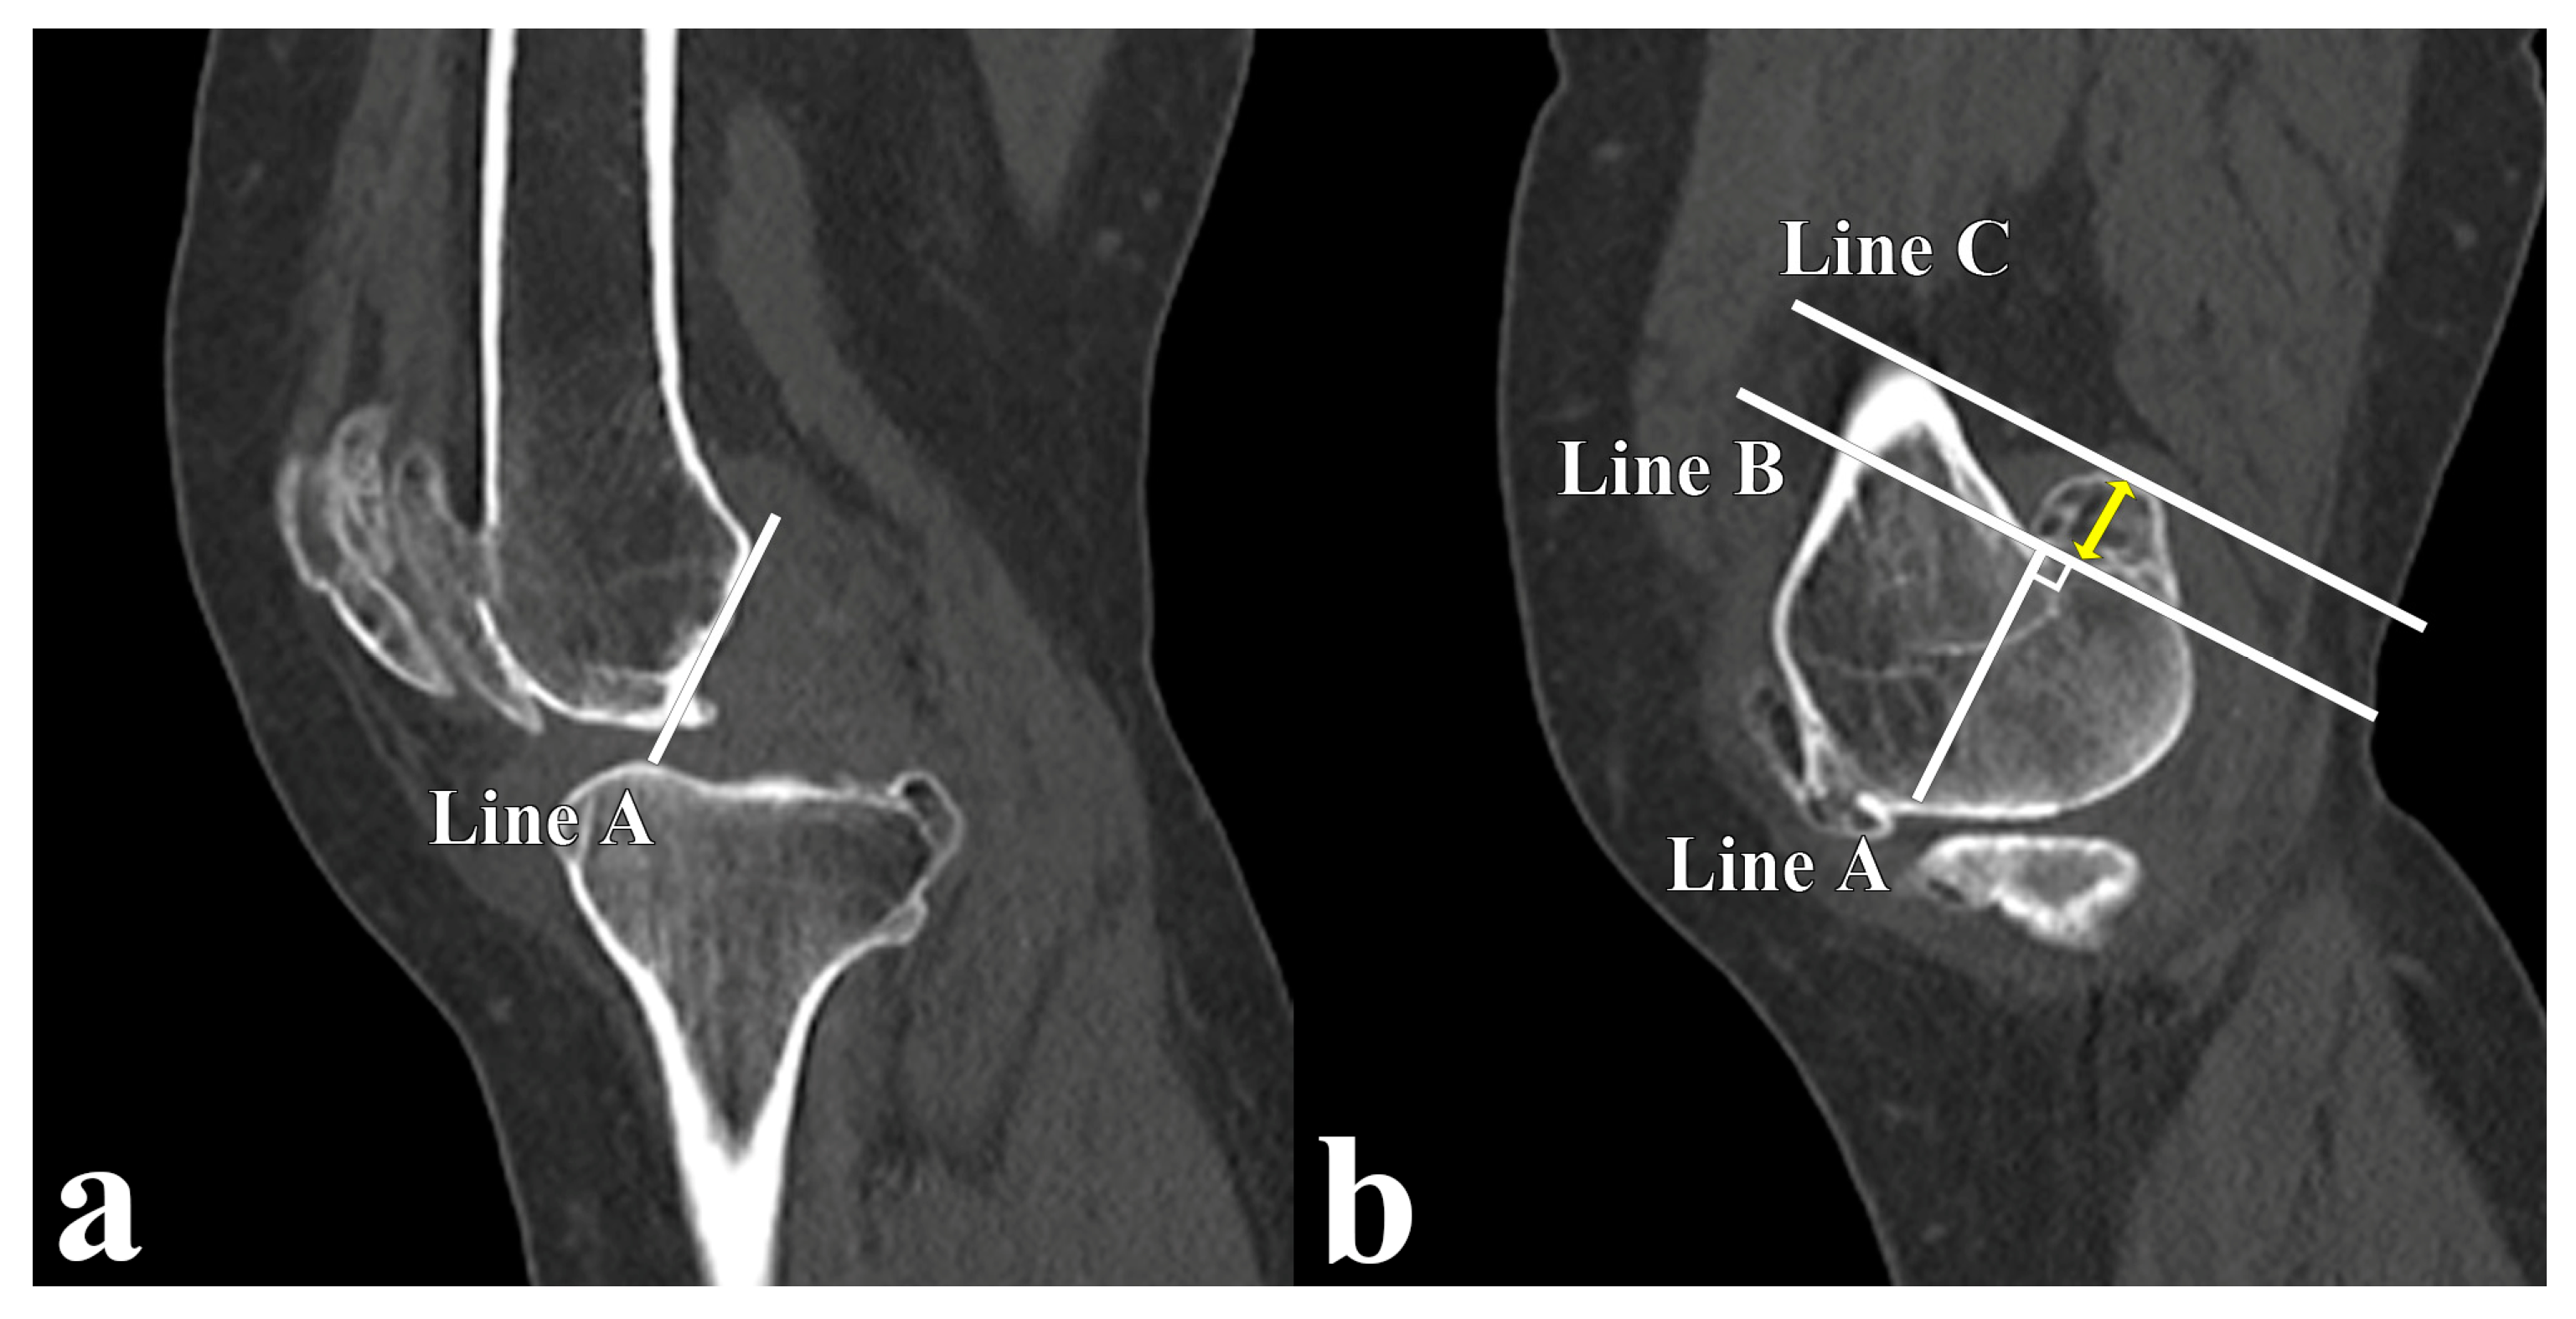

2.3. Radiographic Measurement